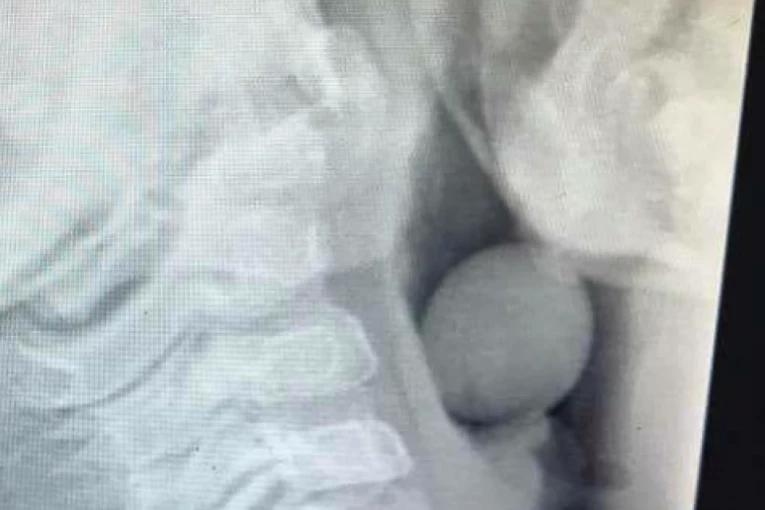

Svet 20:15 30.03.2022 DEČAK ZAVRŠIO U HITNOJ: Šokantan rendgenski snimak pokazuje šta je progutao i počeo da se GUŠI! (FOTO)